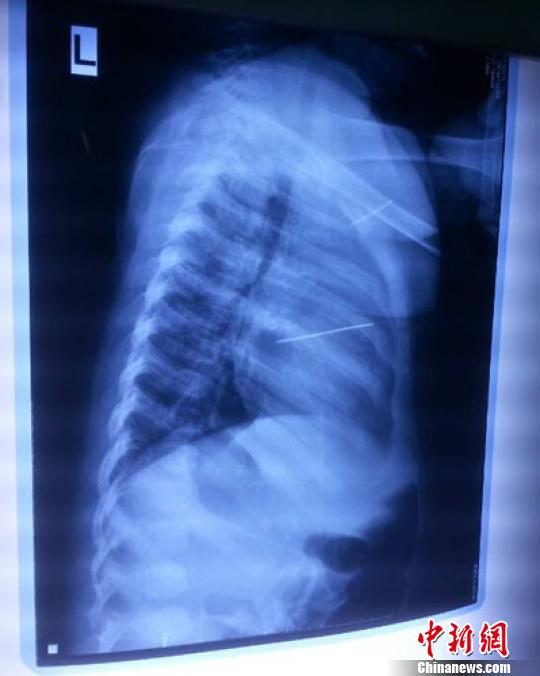

女嬰胸片提示心臟里面扎了一個(gè)縫衣針 蔡迅翔 攝

醫(yī)院胸心外科主任翟波介紹說(shuō),1月22日,小患者彤彤因?yàn)榘l(fā)燒抽搐來(lái)醫(yī)院就診,常規(guī)檢查時(shí)發(fā)現(xiàn)孩子心臟里面扎了一個(gè)縫衣針。

“第二天上午,我們做了個(gè)緊急彩超檢查,發(fā)現(xiàn)針是從患者右心室表面刺入,穿破室間隔,到達(dá)左心房,中間還有一部分損害到二尖瓣。于23號(hào)下午,我們就做了一個(gè)緊急手術(shù),手術(shù)中發(fā)現(xiàn),這枚針已經(jīng)刺入心臟,沒入了右心室的下面,表面已經(jīng)看不到針了,僅能看到一個(gè)小針眼,還在往外滲血,一點(diǎn)一點(diǎn)的滲,心包腔里面大概有100多毫升的出血,心包上一個(gè)洞,針在右心室表面刺入以后,穿過(guò)室間隔,在二尖瓣的上方,進(jìn)入了左心房,在針的四周,有很多纖維沉積物,包繞著這枚針?!钡圆ㄕf(shuō),他們把針取出來(lái)以后,測(cè)量了一下,長(zhǎng)度大概是五厘米,同時(shí)發(fā)現(xiàn)這個(gè)針給患者左心房的后壁造成了一定的損傷,左心房的后壁已經(jīng)損傷了三分之二,還剩下有左心房的外膜,很薄的一層,如果這一層再破的話,這個(gè)孩子將會(huì)引起大出血,很快就會(huì)死亡。